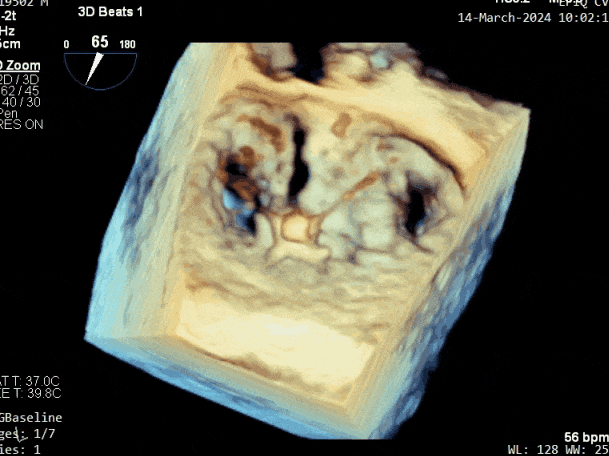

第三个瓣膜夹释放后评估,释放后评估,二尖瓣呈双孔,组织桥张力合适,瓣膜夹轴向与二尖瓣闭合线垂直,无残余反流

2. 本例患者外院超声心动图考虑二尖瓣前叶脱垂,入院后经食道超声心动图明确该患者为二尖瓣后叶活动受限,呈房源性栓系,二尖瓣前叶假性脱垂,超声特征表现为心房功能性二尖瓣反流终末期,呈现出很典型的二尖瓣后瓣环向左室游离壁顶部位移和后叶挛缩表现,同时合并有明显的二尖瓣瓣环扩张、圆形化,左房增大等不利因素,术中通过精准的影像指导和手术操作,成功行TEER,二尖瓣反流程度减轻至微量。